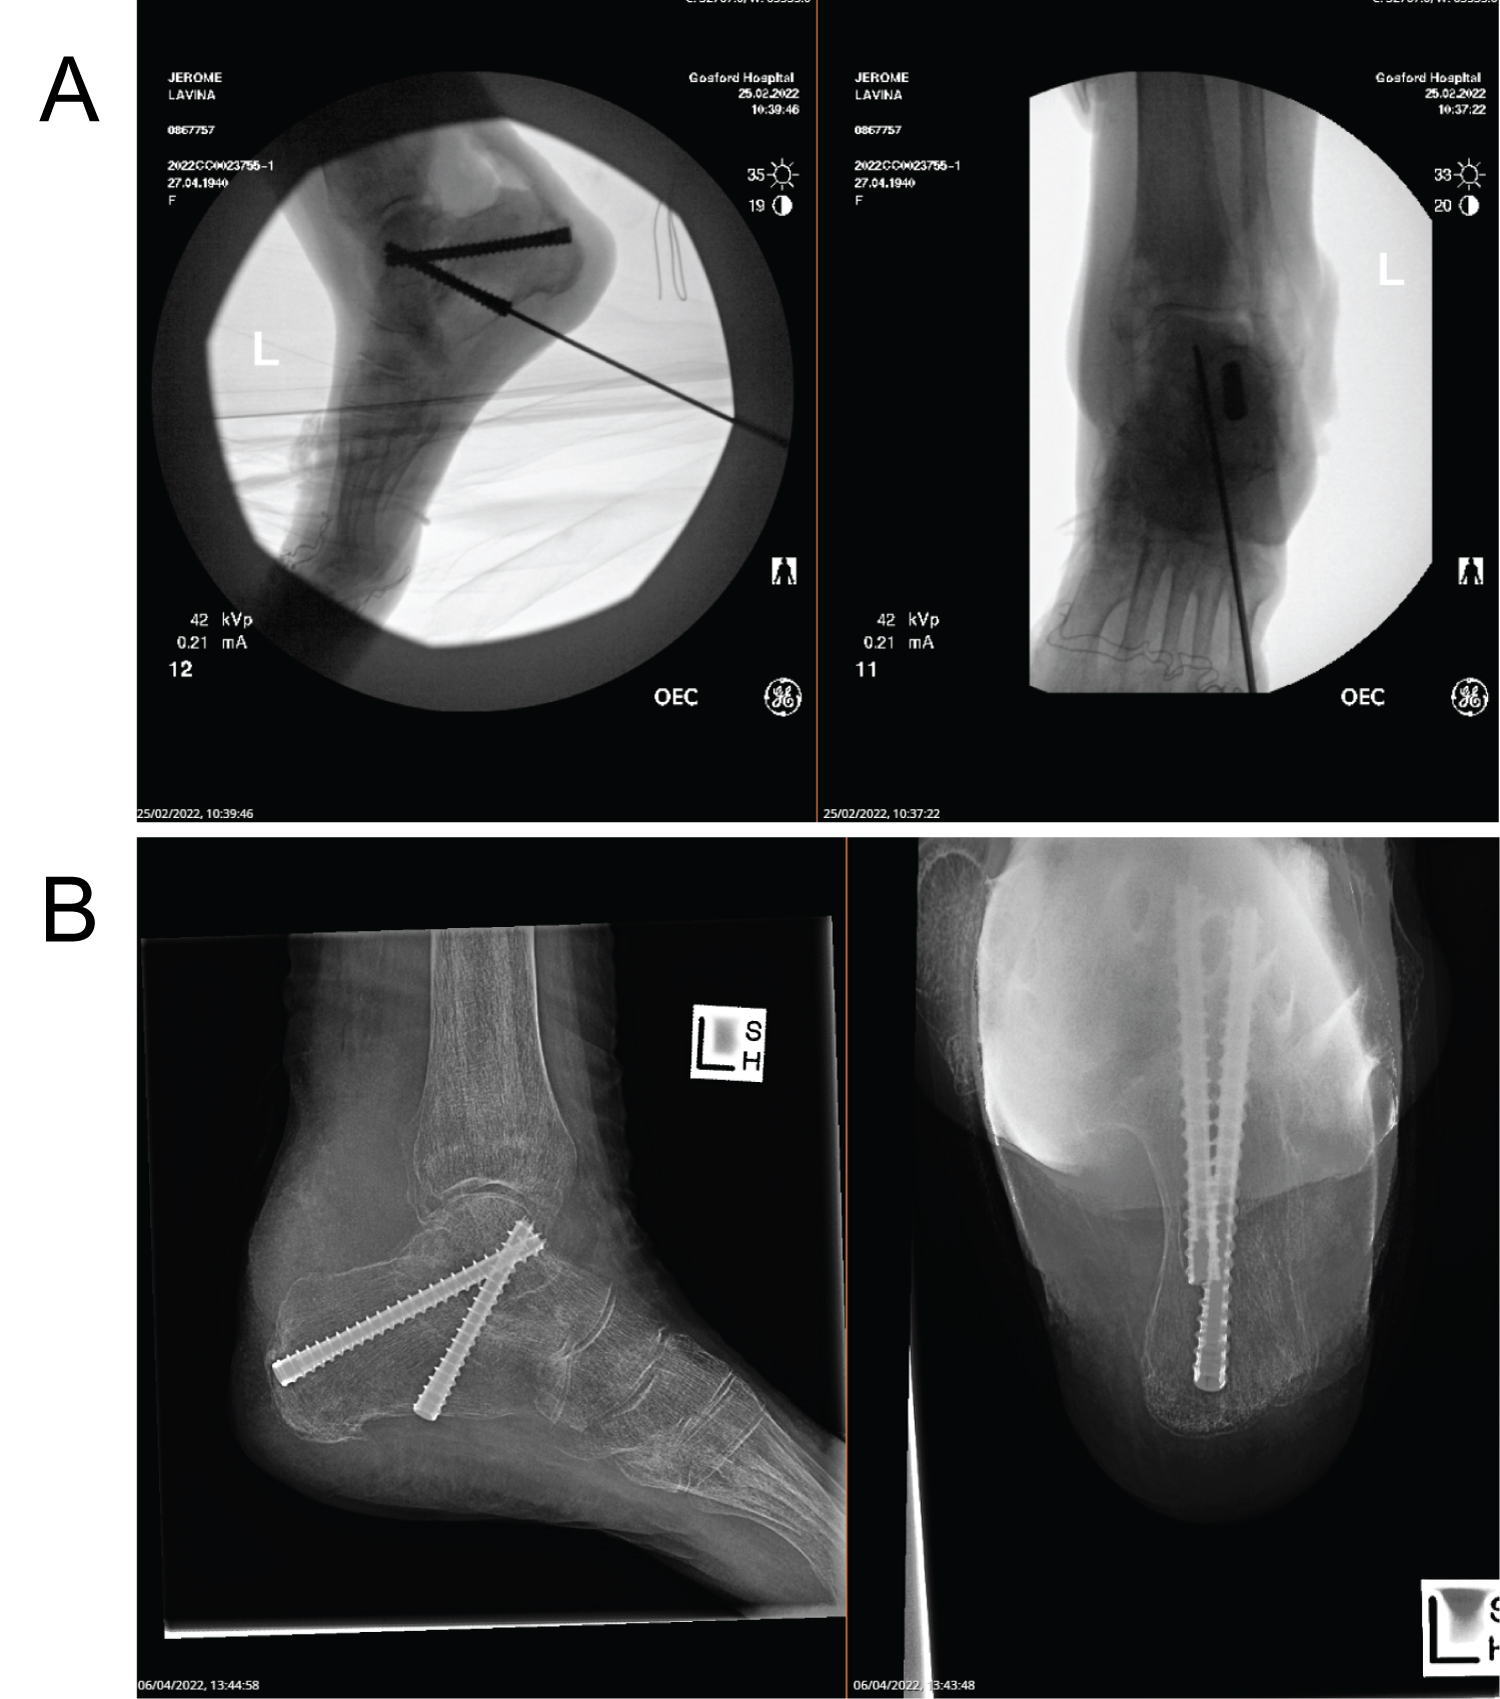

An 81-year-old female had ongoing pain in her left ankle for the past 7 years. It was initially thought to be an ankle sprain when she first presented and was managed non-operatively with analgesia and physiotherapy. She denies any trauma and has been able to weight bear and mobilise on her left leg. There was swelling in the medial aspect of the ankle and with repeated episodes of pain, a plain X-ray was performed. An ankle cyst was found and the patient underwent excision of this cyst. The excisional biopsy provided a diagnosis of synovial chondromatosis. The patient re-presented three years later with massive swelling, severe pain day and night, minimal mobility desperate for a solution. X-ray and MRI findings are seen below (Figure 1 and Figure 2).

Figure 1: X-ray of the left ankle joint performed in 2017 showing edema and calcification of soft tissue. View Figure 1

Surgical management was indicated in her case where an extensile lateral approach whilst visualizing the subtalar joint was utilised to excise the cystic mass. Two pieces of fibrous grey-white tissue 36 × 30 × 24 mm and 43 × 33 × 28 mm were removed during the procedure. Subtalar fusion was then performed with Acutrak headless compression screws (Figure 3a and Figure 3b).

Figure 3: (a) Showing intraoperative insertion of Acutrak Screws; (b) Showing two Acutrak screws 7.5 mm each used for subtalar fusion post operation. View Figure 3